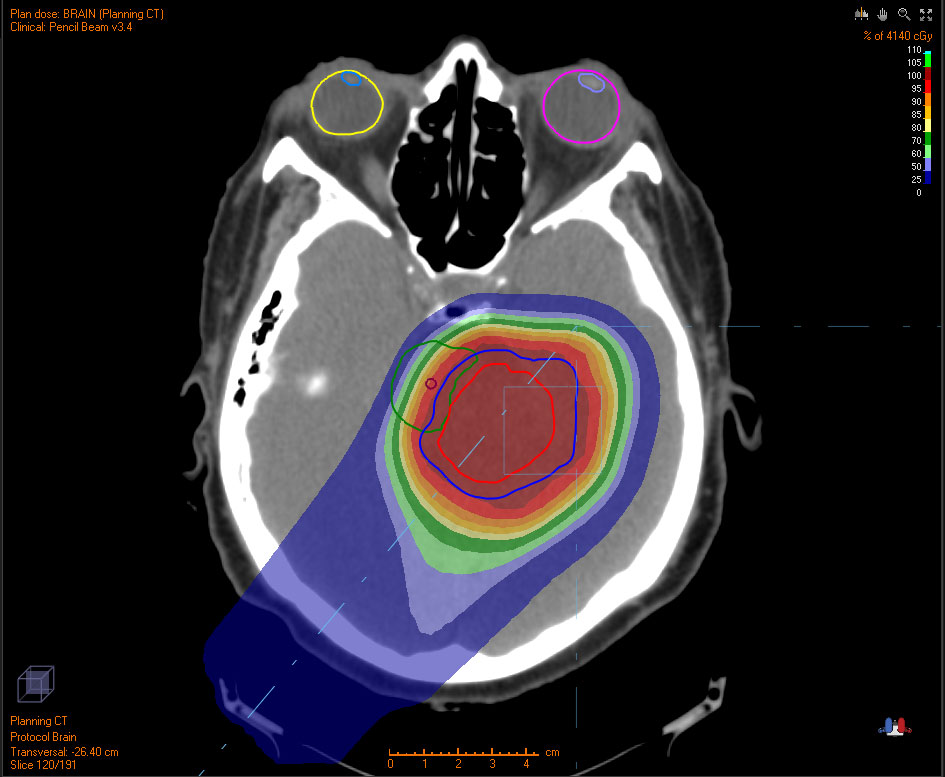

Proton therapy is an advanced form of radiation treatment that targets tumors with precision.

Unlike traditional radiation, protons stop at a certain depth and do not continue to travel through the body. This allows surrounding healthy tissues to be undamaged by radiation.

Proton therapy is useful for tumors near vital structures such as the brain, spinal cord, optic nerve, heart, lung, bladder and rectum, where treatment needs to be more focused to minimize damage to healthy tissues.

Below are examples of tumors treated with proton therapy and standard X-rays. In both cases, the tumor is treated with radiation. However, proton therapy delivers most of the radiation directly to the tumor, leaving much of the surrounding tissue unaffected. In contrast, standard X-ray radiation exposes a larger area of healthy tissue to radiation.